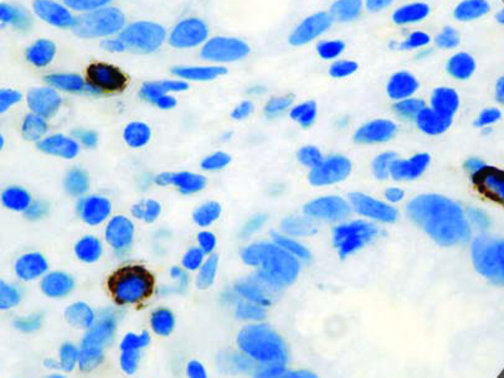

It is the ICU physician who is most likely to witness one of the deadliest manifestations of the abnormal immunological response, the cytokine storm syndrome (CSS). This response is also referred to by some as the cytokine release syndrome (CRS). CSS is characterized by continuous activation and expansion of macrophage and lymphocyte populations, which secrete large amounts of cytokines, causing the cytokine storm. This massive cytokine release is akin to hemophagocytic lymphohistiocytosis (HLH) disease, a syndrome characterized by initial unchecked and persistent activation of cytotoxic T lymphocytes and NK cells.

Clinical and laboratory manifestations of HLH include fever, enlarged liver and/or spleen, neurologic dysfunction, coagulopathy, liver dysfunction, cytopenias (i.e., low levels of erythrocytes, leukocytes, and/or platelets), hypertriglyceridemia, hyperferritinemia, hemophagocytosis, and eventually diminished NK cell activity as the immune system becomes progressively paralyzed. HLH can be familial (primary HLH) or secondary to another disease process (sHLH), such as rheumatic disease, in which it is referred to as macrophage activation syndrome (MAS, characterized by elevated ferritin).